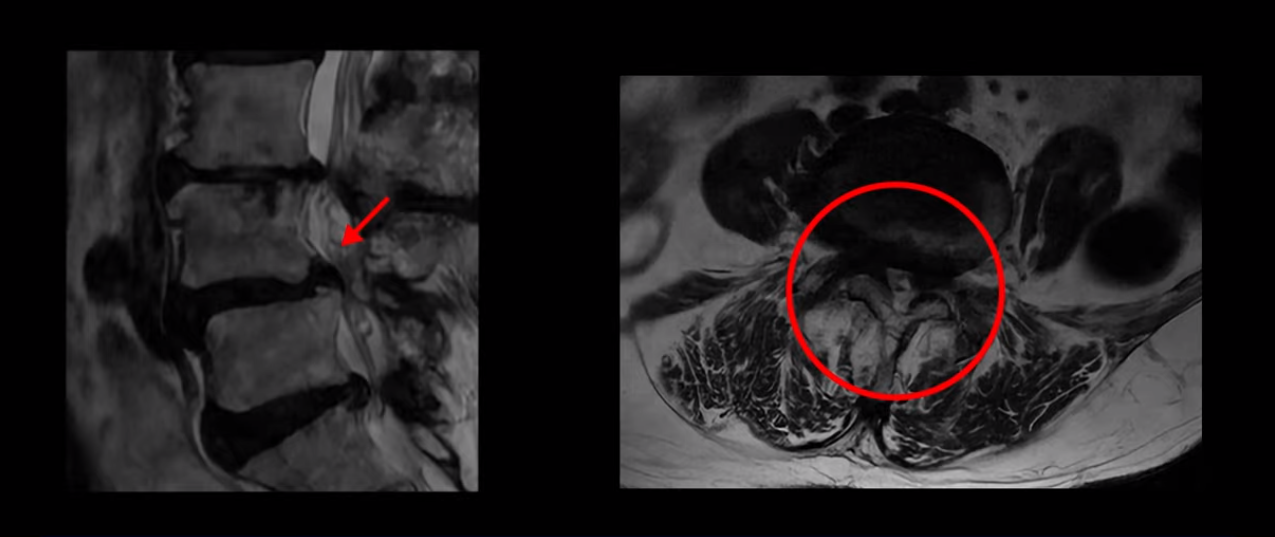

제가 먼저 이분 MRI를 보고 설명해 드린 후 어떻게 이런 분들을 수술 없이 허리 기능재활치료로 호전시킬 수 있는지 자세히 설명드리겠습니다. 이분 허리가 보시다시피 여러 마디가 퇴행되어 있고

4번 5번에는 뼈가 밀려 나간 전방전위증도 있습니다.

X-ray로 보면 뼈가 밀려 나간 게 더 잘 보입니다.

4번 5번 마디를 자세히 보면 심한 중심성 협착이 있어서 신경 구멍이 매우 좁아져 있습니다.

또 신경 가지가 빠져나가는 추간공도 매우 좁아져 있습니다.